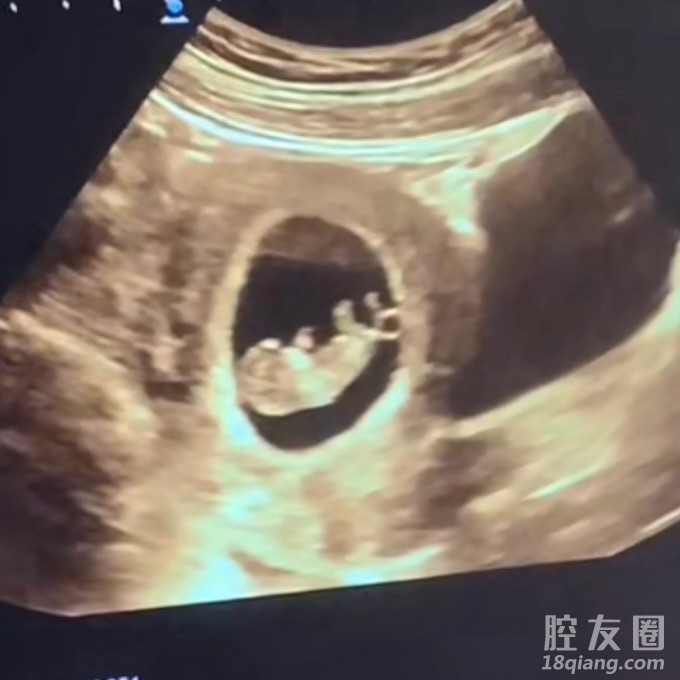

爸爸姓鞠,腔友们有没有好的名字推荐一下

这个姓起名真的太难了

图片是刚满十周的时候~